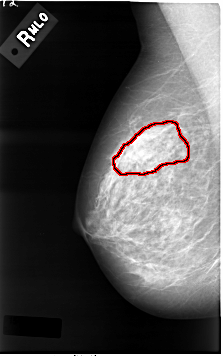

C_0001_1.RIGHT_MLO

RIGHT_MLO LINES 4616 PIXELS_PER_LINE 2888 BITS_PER_PIXEL 12 RESOLUTION 50 OVERLAY

FILE: C_0001_1.RIGHT_MLO.OVERLAY

TOTAL_ABNORMALITIES 1

ABNORMALITY 1

LESION_TYPE MASS SHAPE IRREGULAR MARGINS ILL_DEFINED

ASSESSMENT 4

SUBTLETY 3

PATHOLOGY MALIGNANT

TOTAL_OUTLINES 1

BOUNDARY